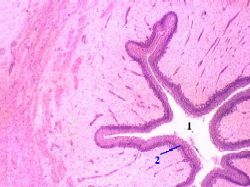

1. а) Слизистая

оболочка включает два компонента:

переходный

эпителий (2) и

собственную

пластинку (3) из рыхлой

соединительной ткани.

б) Мышечной пластинки нет.

2. а) Что касается переходного

эпителия (2), то это

разновидность многослойного

эпителия. |

б) Иными словами, с базальной мембраной

контактирует

только нижний, базальный

слой клеток.

3. Кроме этого слоя, имеются ещё

два: |

промежуточный

слой и

поверхностный,

содержащий крупные клетки

куполообразной формы.

4. а) При

растяжении соответствующего участка

мочеточника форма поверхностных клеток

изменяется:

клетки уплощаются.

б) Однако препарат

приготовлен, естественно, из нерастянутого

органа,

так что клетки имеют обычную (куполообразную)

форму. |

1. а) Подслизистая основа

(4), как и собственная пластинка (3) слизистой

оболочки, образована

рыхлой

волокнистой соединительной тканью.

б) Из-за

отсутствия в слизистой оболочке мышечной

пластинки,

чёткой границы между этой оболочкой и

подслизистой основой нет.